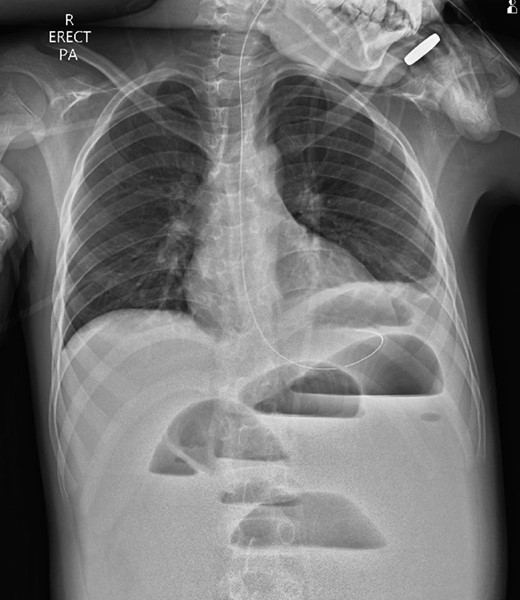

A 10-year-old boy presented unwell with generalized peritonitis after 3 days of abdominal pain, nausea and anorexia. He had a low-grade fever but all other vitals were within normal limits. Blood tests showed a raised white cell count of 16 × 109 with neutrophilia and raised C-Reactive Protein of 127 mg/l. Laparoscopy revealed generalized purulent peritonitis secondary to perforated appendicitis. Appendicectomy was performed and the appendiceal stump was secured. Lavage of the abdomen was performed with a minimum of four litres of warmed normal saline. Fluid was suctioned, an abdominal drain was placed and the pneumoperitoneum was deflated. By the second postoperative day, he developed an ileus with persistent vomiting (Fig. 1). This was managed conservatively with nasogastric intubation, bowel rest, electrolyte replacement and fluid therapy. It became clear by the fifth postoperative day that the patient had intestinal obstruction. On examination, he had a distended abdomen, with intractable nausea and vomiting. Blood tests revealed a normal white cell count and potassium remained at 3.3 despite supplemental intravenous replacement. Abdominal X-ray revealed a small bowel obstruction and he was taken back to theatre for an emergency laparotomy (Figs 2 and 3). A small bowel volvulus was discovered, with no evidence of intestinal malrotation. The volvulus involved a segment of distal jejunum to proximal ileum causing complete small bowel obstruction.

Erect chest radiograph on day 5 more consistent with small bowel obstruction.